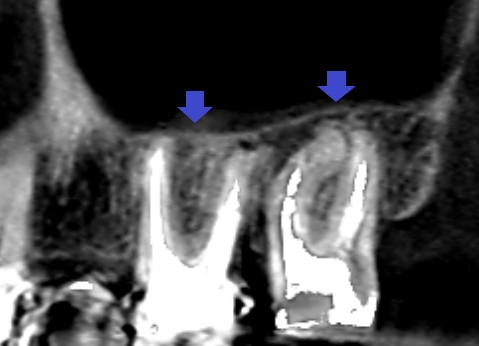

精密根管治療6カ月後のCT画像です。上顎第一大臼歯と第二大臼歯共に根の先にあった大きな膿の影が消失し、上顎洞内にあった上顎洞炎の白い肥厚も消えてきています(青い矢印のところ)。

大きい膿でしたが精密根管治療により膿が消失し、同時に歯性上顎洞炎も改善しました。今回のように、歯性上顎洞炎は副鼻腔炎の一つですが根管治療のみで治ることもあるのです。上顎洞炎に根尖病変が近接している場合は、まず根管治療をしてみることをお勧めします。